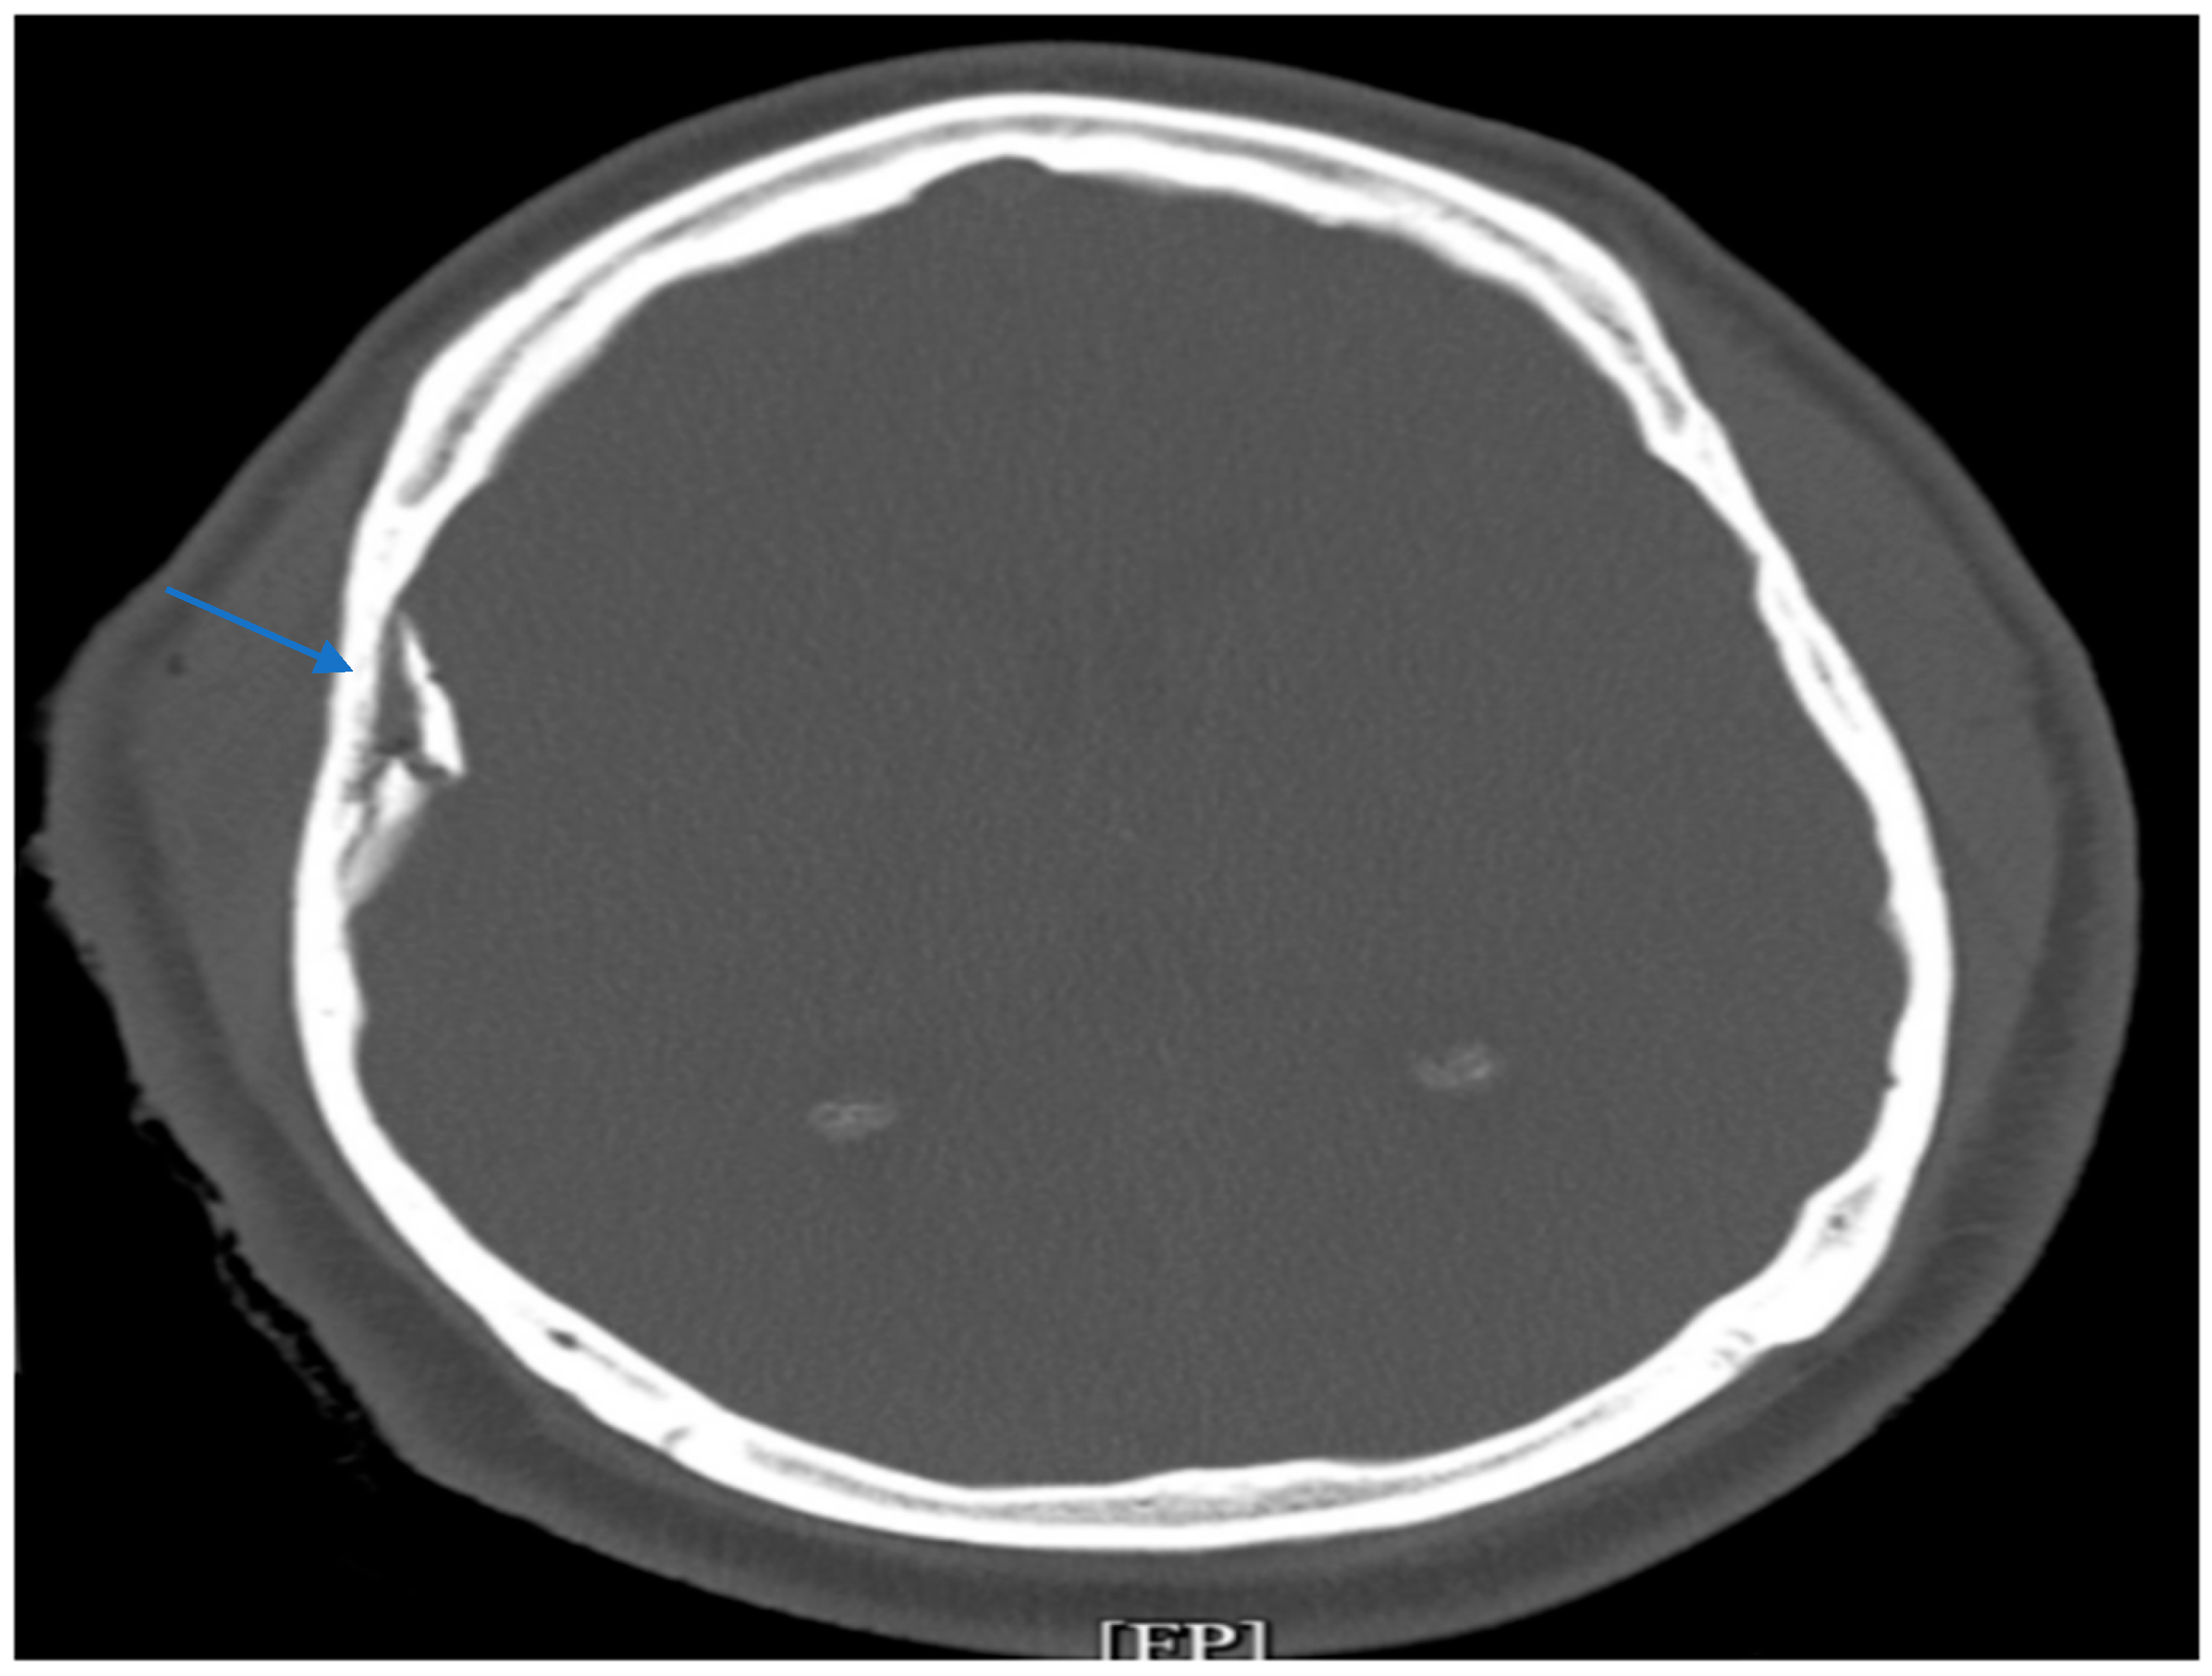

Non-contrast head CT demonstrated (Figure 1) an acute, depressed, comminuted right temporoparietal skull fracture with a small underlying contusion, scattered subarachnoid hemorrhage, and mild pneumocephalus (Figure 1). According to the Marshall CT Classification, this corresponded to Diffuse Injury II. His trauma severity was significant, with an Injury Severity Score (ISS) of 29, reflecting severe polytrauma. Imaging also showed bilateral displaced humeral head fractures with posterior glenohumeral subluxation. Neurosurgery performed urgent craniotomy, elevated the depressed bone fragments, evacuated the contusion, and placed an external ventricular drain (EVD) for continuous intracranial pressure (ICP) monitoring and cerebrospinal fluid diversion.

Figure 1. CT imaging demonstrating an acute depressed and comminuted right temporoparietal skull fracture (blue arrow).